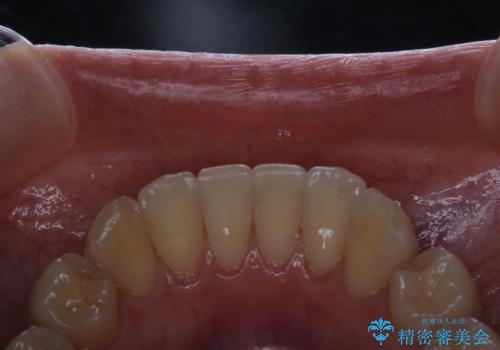

- インビザラインでのマウスピース矯正が終了したため、きれいにクリーニングして口元を明るい印象にしたいとのことでした。PMTC60分コースを行いました。

矯正治療が終わり、せっかくきれいになった歯並びも、虫歯・歯周病などになってしまっては元も子もありません。

矯正治療やセラミックなどによる被せ物の治療終了のタイミングではクリーニングを行い、汚れや着色の除去、歯と歯の間・歯と歯肉との境目などのケアをしっかりすることをおすすめしています。

ご自身での歯ブラシ・セルフケアを行うと同時に、定期的なクリーニング(PMTC)を行うことで、いつまでも健康な歯を保つことができます。